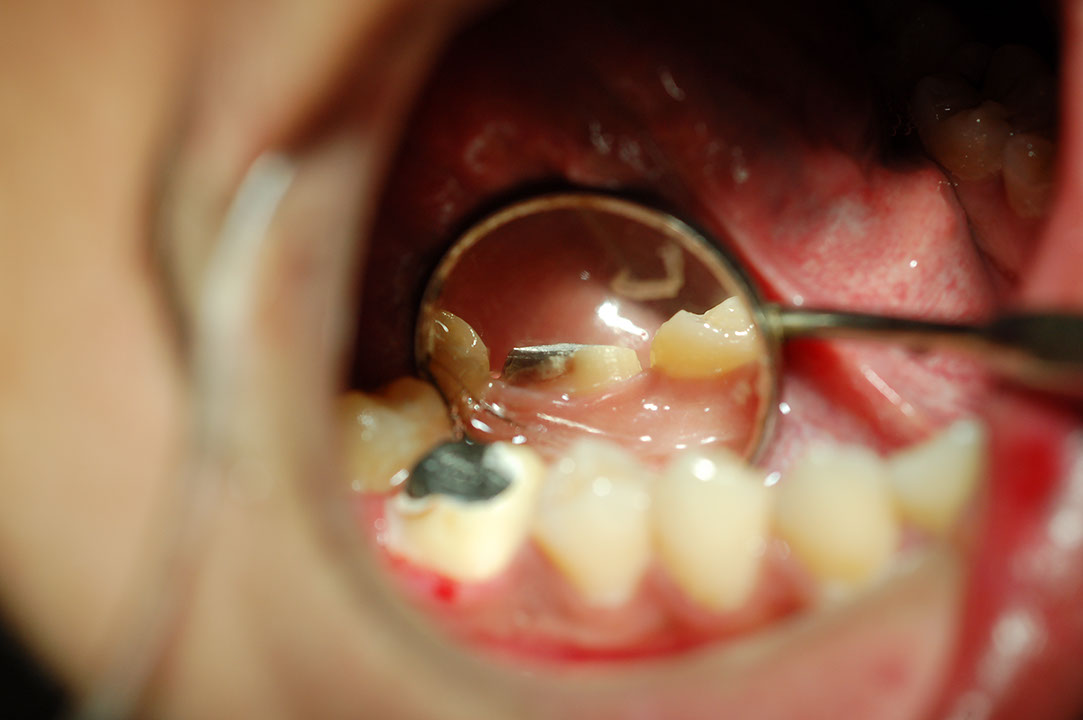

Post 5f1.JPG

光牙醫